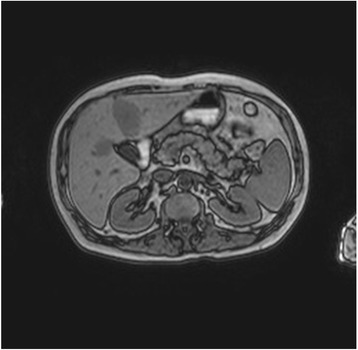

A 54-year-old man presented with small cell lung cancer (SCLC) and metastases of the brain, liver, adrenal glands and mediastinal lymph nodes. Immunohistochemically, tumor cells were positive for CD56 and TTF1. The patient had a 30-year history of cigarette smoking and his past medical history was significant for arterial hypertension and diabetes. He only took medications for back pain and did not drink alcohol. Given his performance status, we considered first-line chemotherapy with cisplatin and etoposide. A blood test before the start of chemotherapy showed normal renal and liver functions but high serum lipase levels (1343 U/L, normal value 13–60 U/L). Further tests revealed elevated levels of neuron-specific enolase (NSE) (173.9 μg/L), carcinoembryonic antigen (220.7; normal value < 5 μg/L) and serum amylase (379; normal value 1–100 U/L). Although progastrin-releasing peptide was recently identified as a biomarker of SCLC, we chose not to analyze it as it has not yet been introduced into clinical practice. Pancreatic isoamylase value was 339 U/L (normal value 17–115 U/L). Serum calcium and other electrolytes were normal. The patient was asymptomatic. Magnetic resonance imaging (MRI) of the abdomen performed to exclude pancreatic lesions and/or pancreatitis was negative (Fig. 1).

Fig. 1.

MRI was negative for acute pancreatitis and other diseases